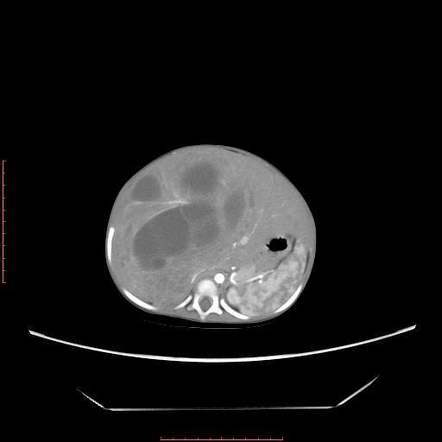

Nephroblastomatosis

multifocal/diffuse nephrogenic rests–> persistence of metanephric blastema

precursor to wilms

Associated with: BW, WAGR, and hemihypertrophy